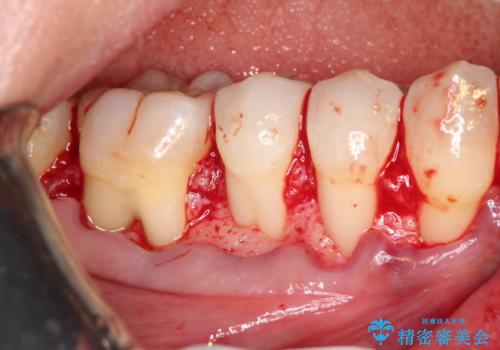

結合組織移植術を行う方法を提案しましたが、傷口が口蓋にもできるのが嫌だとのことで、代替案としてバイオマテリアルを併用した根面被覆術を計画致しました。

治療対象部位は右下4,5,6番の3本です。

幸いなことに術後の痛みがほとんどなく、翌日には痛み止めも飲まずに済んだとのことでした。

治癒経過も良好で、患者様も満足されていました。また、知覚過敏も減ったとの事でした。